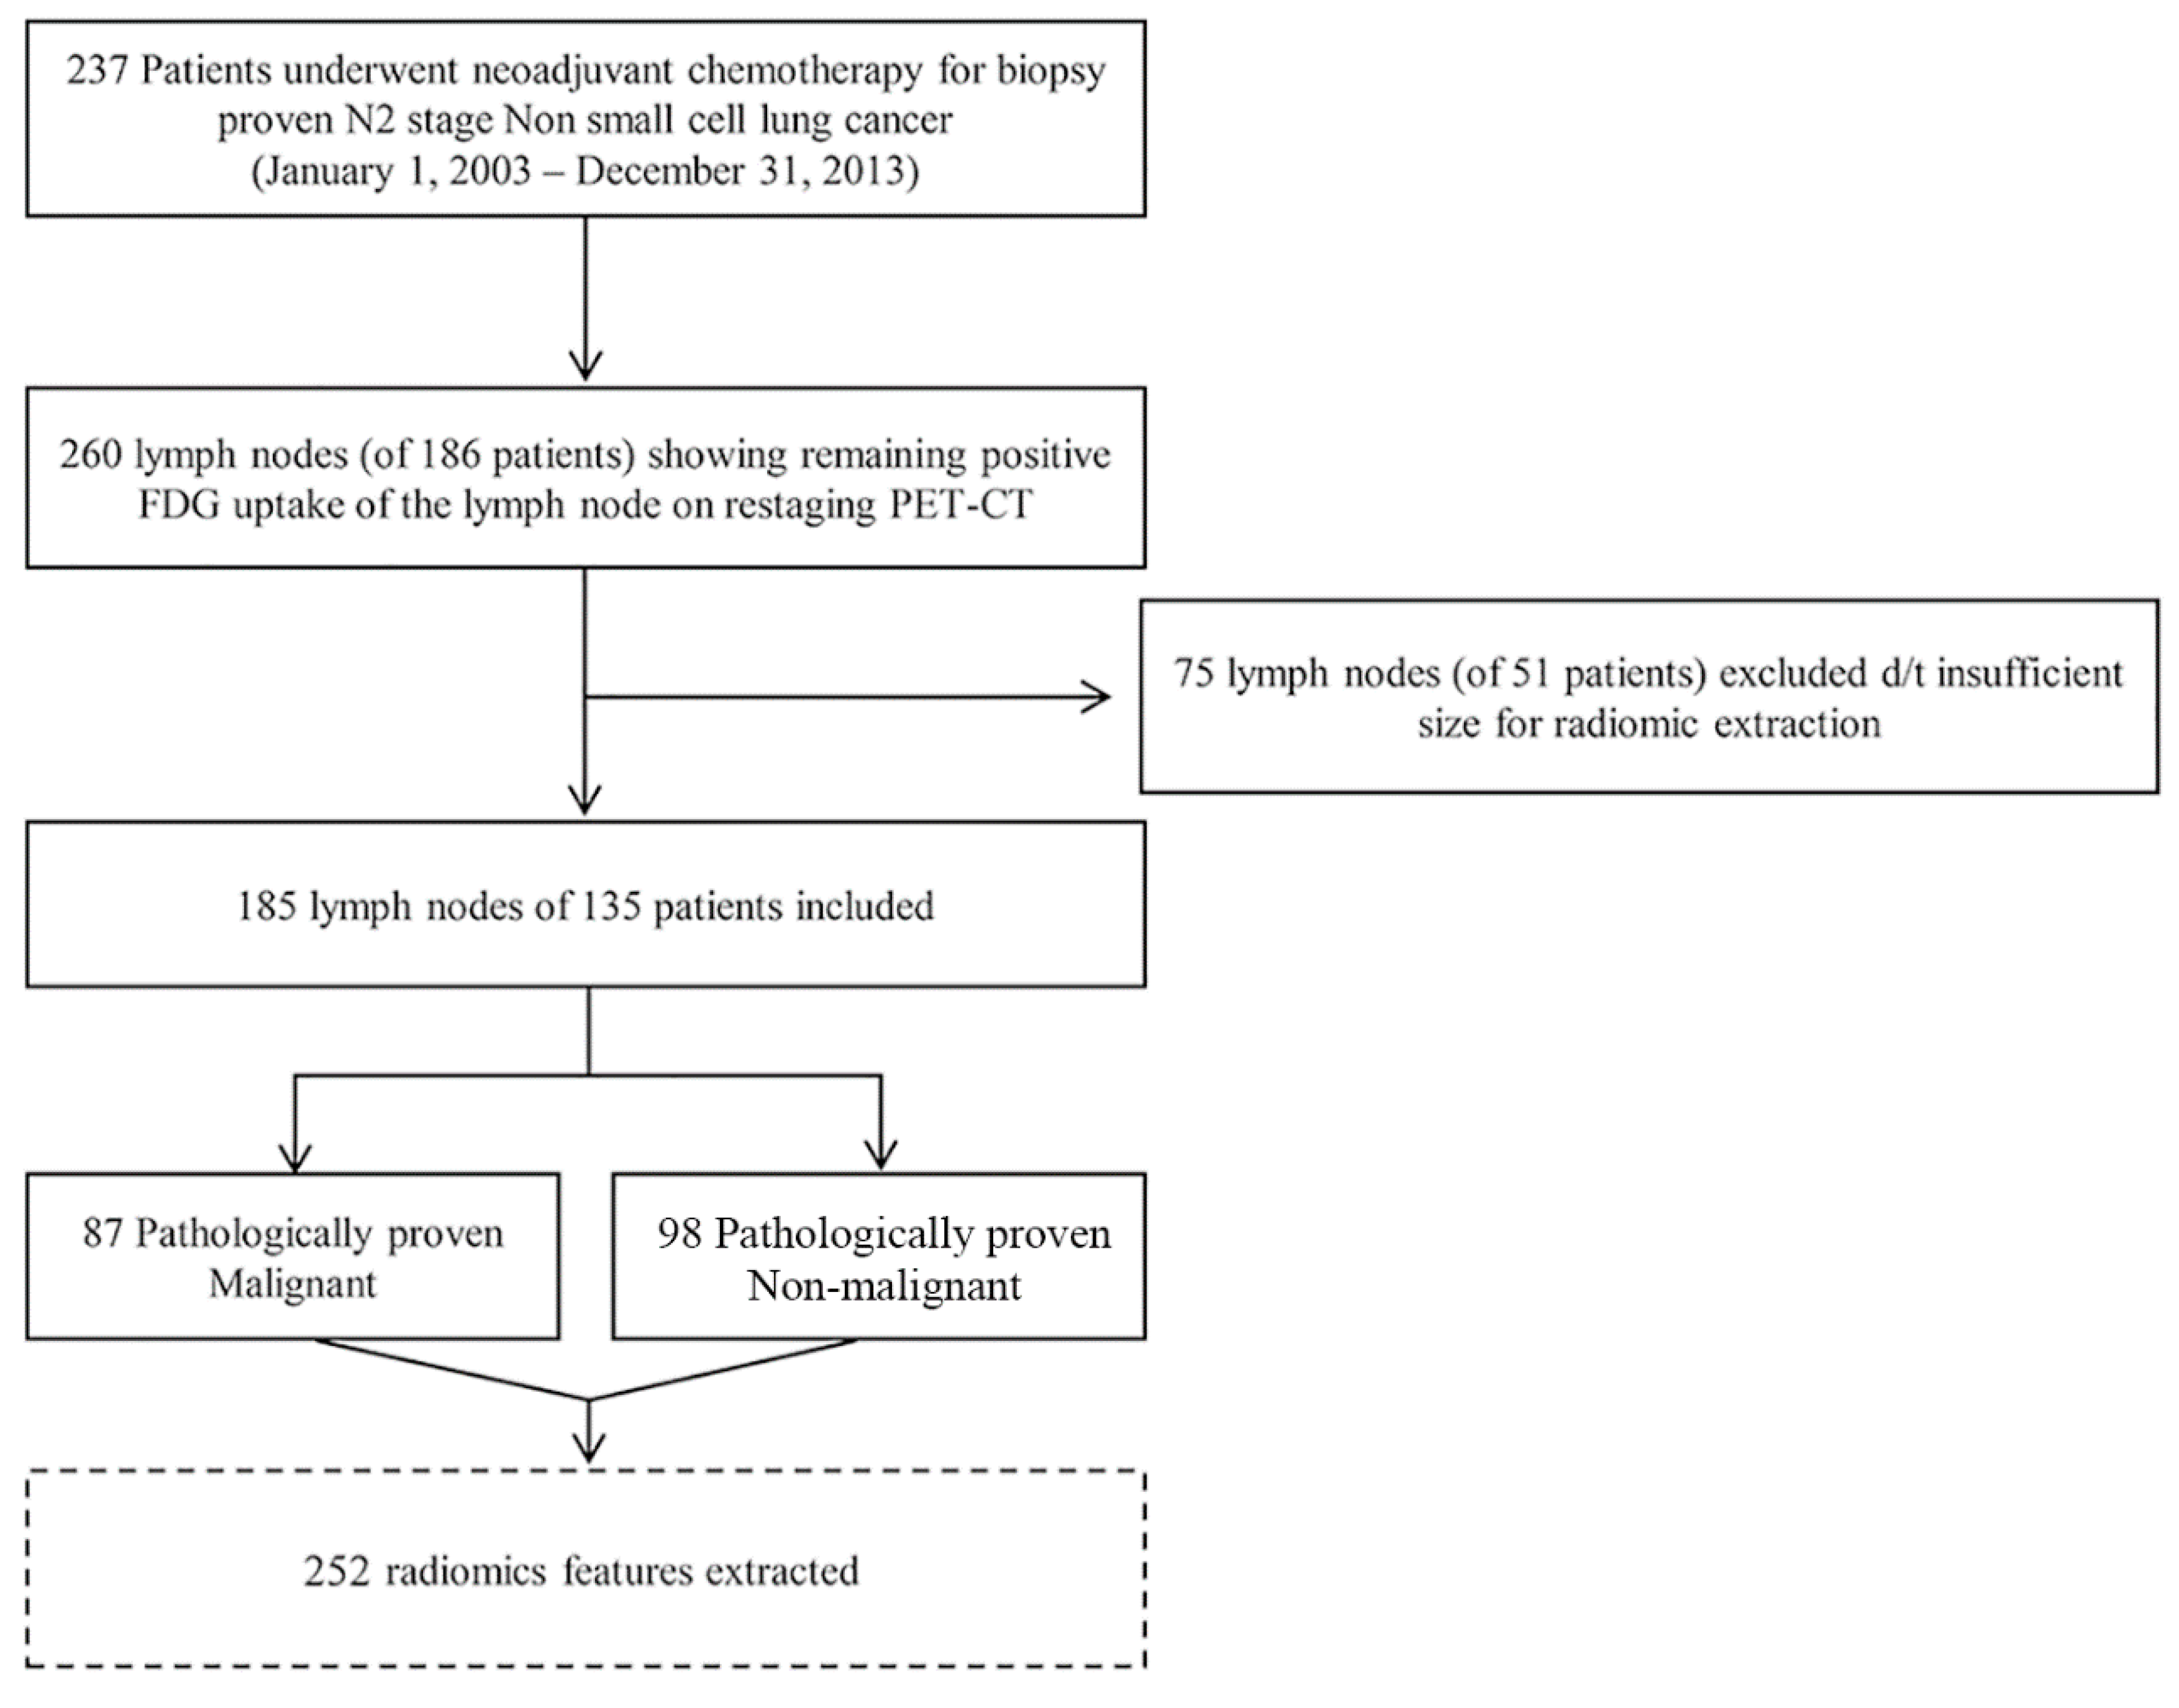

4.1. Patients